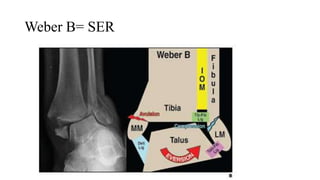

Weber B= SER

SER ( Ngữa- xoay ngoài)

• SER1: Đứt d.c chày mác trước

• SER2: Gãy xương mác theo đường chéo hoặc

chéo xoắn

• SER3: Đứt d.c chày mác sau hoặc nhổ mắt cá

sau

• SER4: Đứt d.c denta hoặc nhổ mắt cá trong

gãy ngang